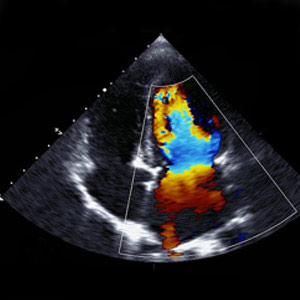

Doppler Study – (Upper Limb/Lower Limb)